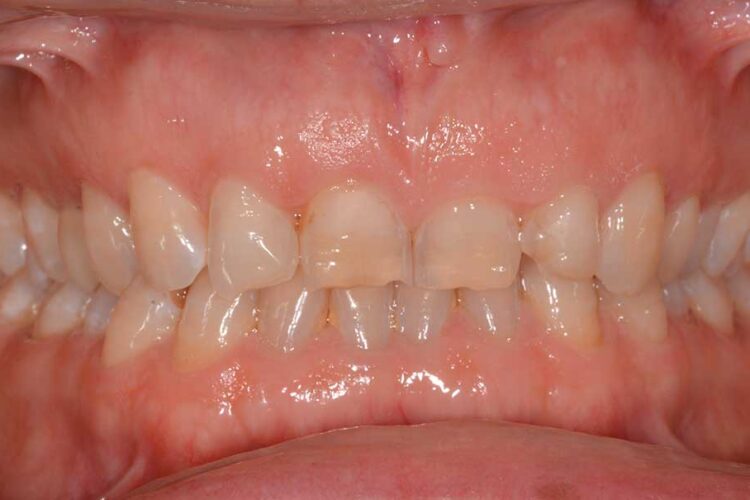

Ortodonzia allineatori – caso clinico 2